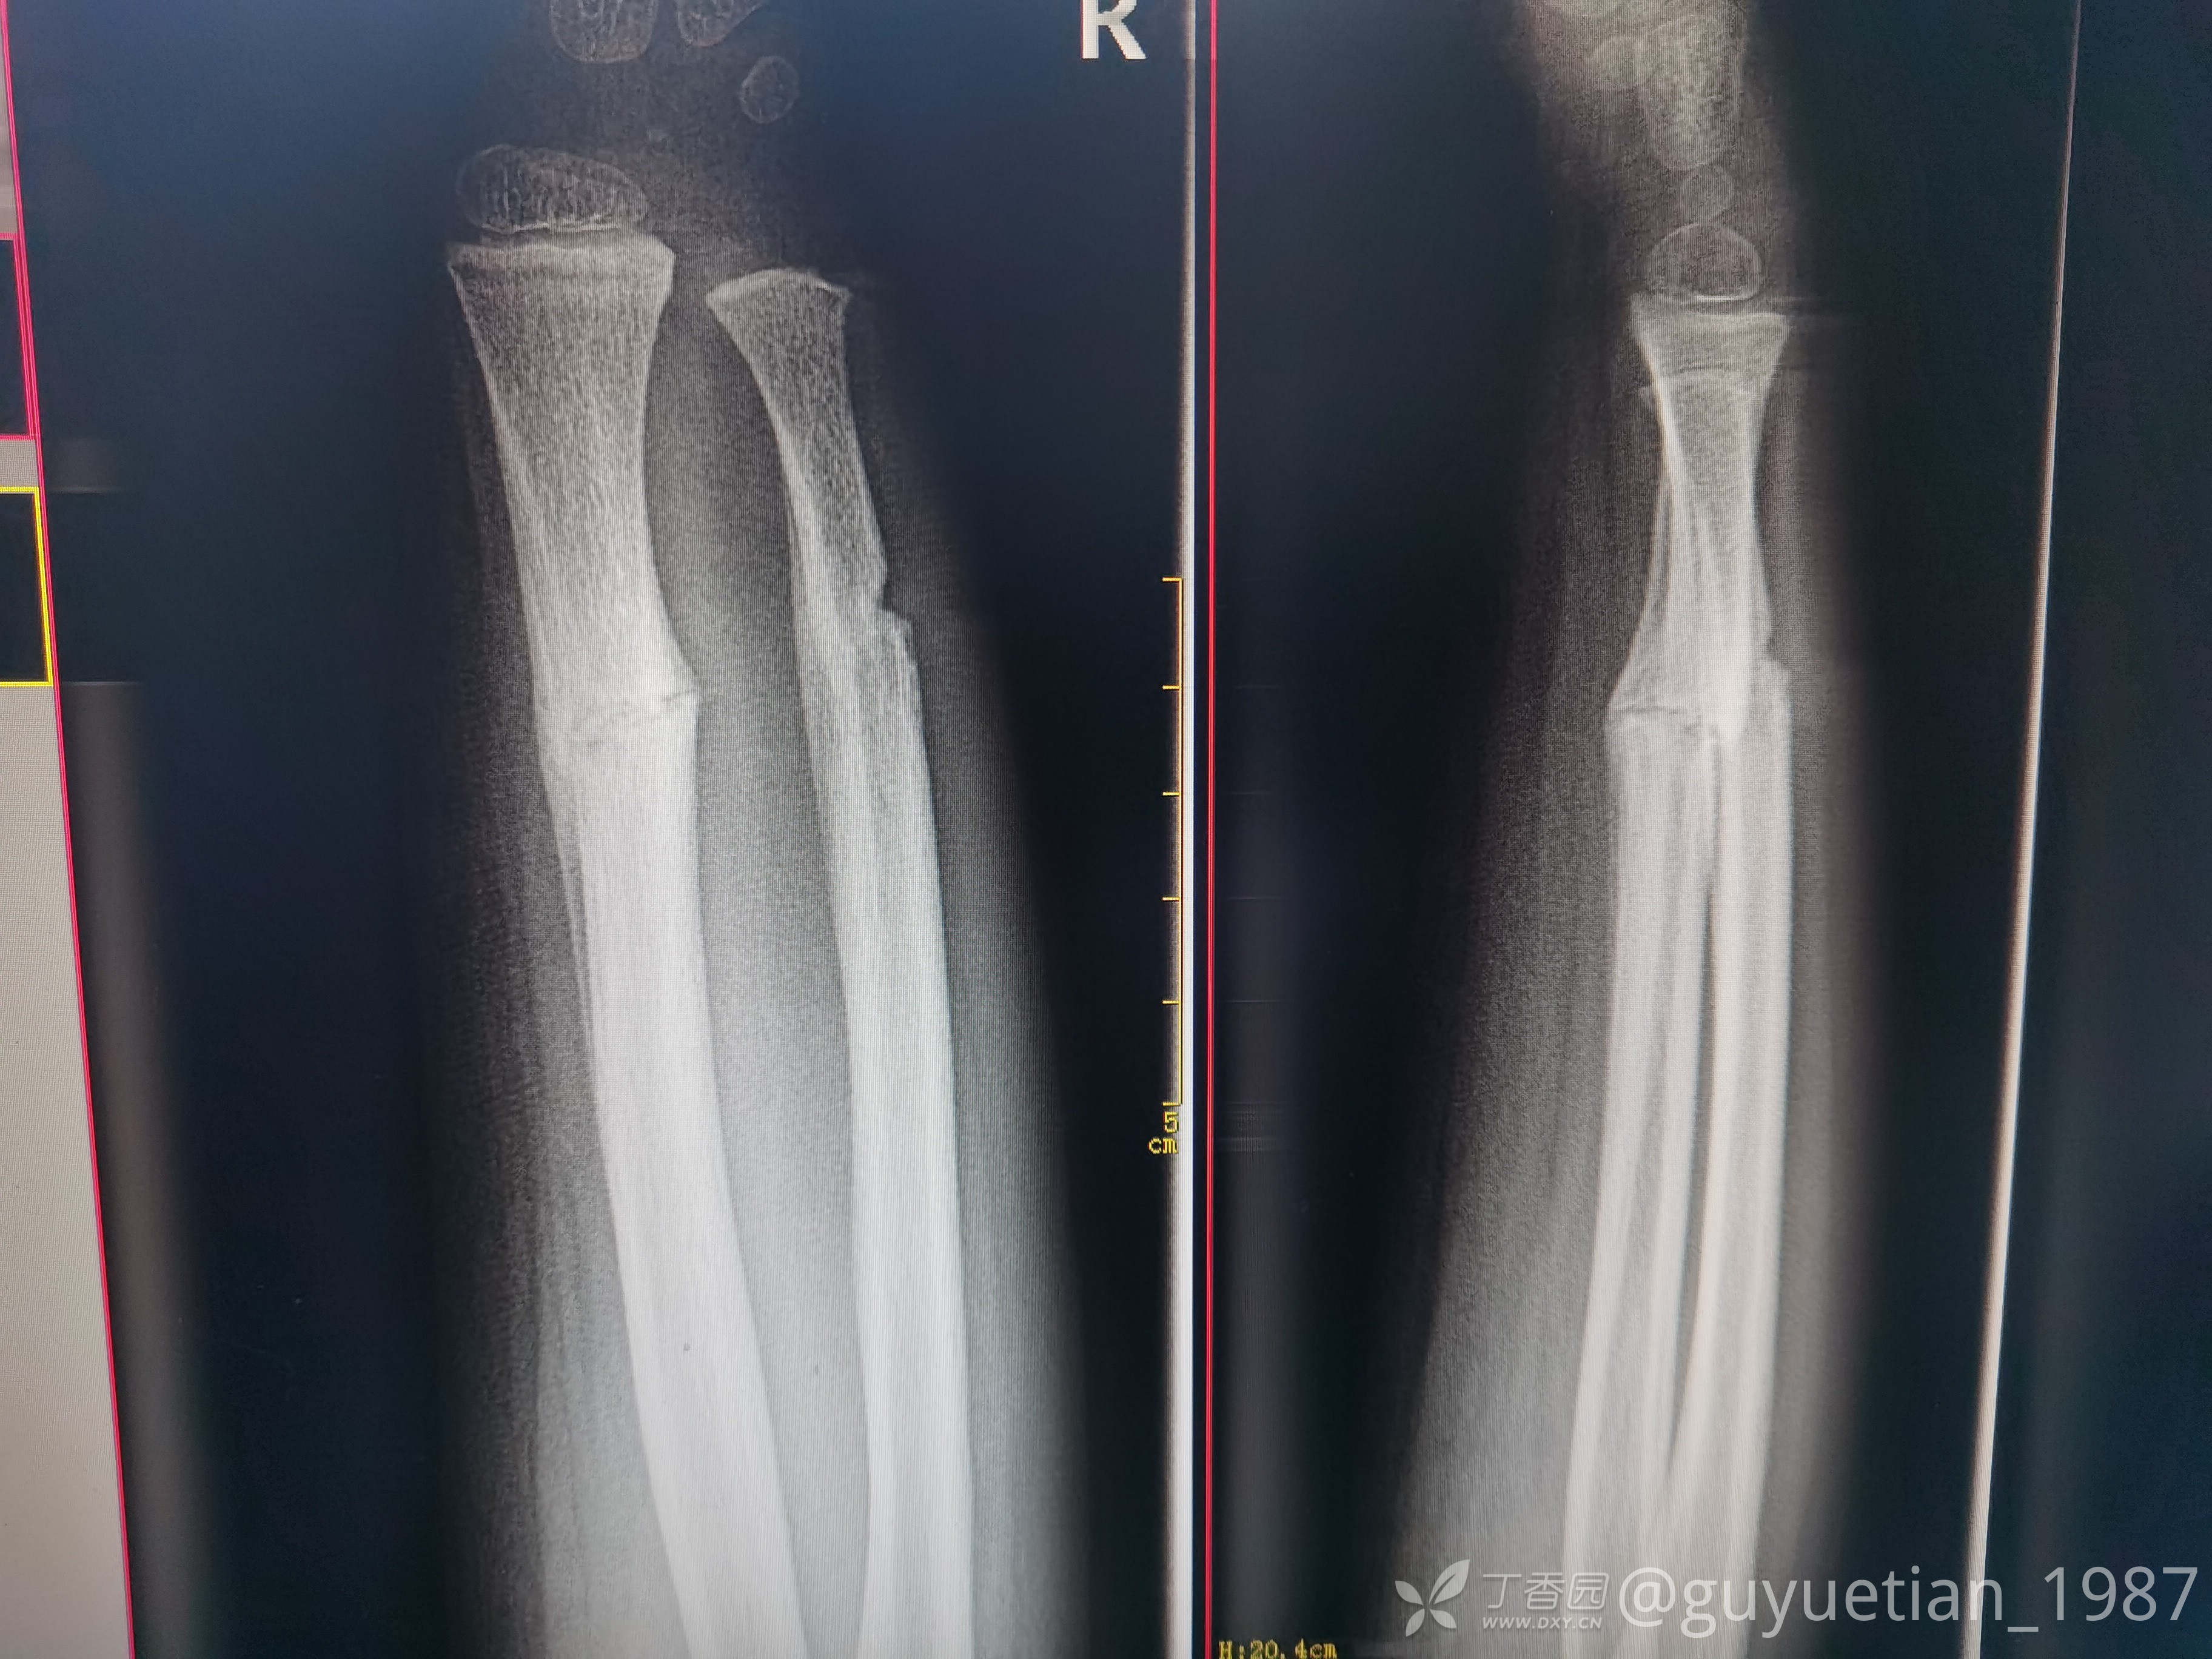

2周后复诊,出现骨痂

3周后,明显看到骨痂,开始塑形。